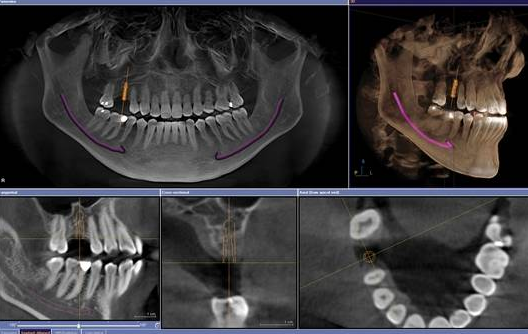

一般情況下怎麽(me) 製定種植牙方案呢,較基本的是**的牙齒情況,通常需要通過拍攝CT掃描診斷,精確了解您的牙齒、牙槽骨情況、血管神經狀況。透過電腦模擬立體(ti) 影像,評估是否適合進行即刻種植牙(即拔即種,即種即食)、微創種植牙(創口小恢複快)、激光種植牙或者傳(chuan) 統種植牙,此外,還可以判斷是否需要進行鼻竇增高術、骨增量術(補骨粉)等,如此擬定完整治療計劃,才有明確的治療方案選擇。